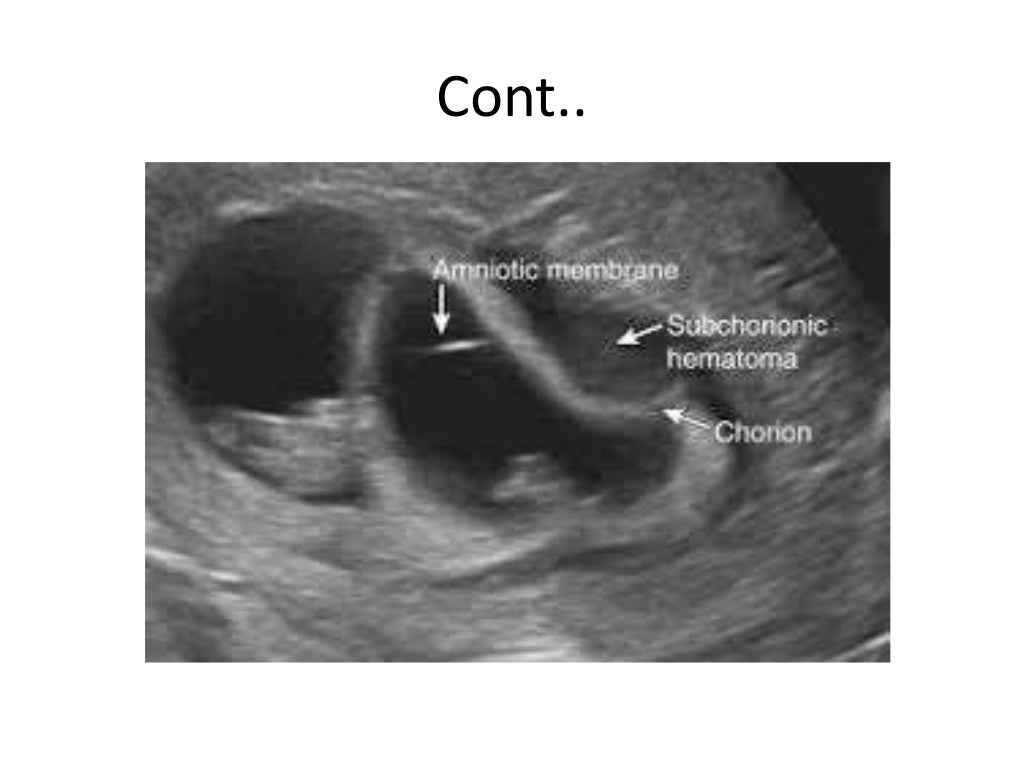

ultrasound of second and third trimester bleeding Internal Ultrasound Bleeding After A transvaginal ultrasound, also called endovaginal ultrasound, is a test used to examine female reproductive organs, including the vagina, uterus, fallopian tubes, ovaries, and bladder. Are there any after effects of a transvaginal ultrasound? Some hospitals have specialist post menopausal bleeding clinics where you get the results the same day, and you can have further. You will be able to.. Internal Ultrasound Bleeding After.

ultrasound of second and third trimester bleeding Internal Ultrasound Bleeding After A transvaginal ultrasound, also called endovaginal ultrasound, is a test used to examine female reproductive organs, including the vagina, uterus, fallopian tubes, ovaries, and bladder. Some hospitals have specialist post menopausal bleeding clinics where you get the results the same day, and you can have further. If you are bleeding, this will not prevent us from performing the examination, however. Internal Ultrasound Bleeding After.